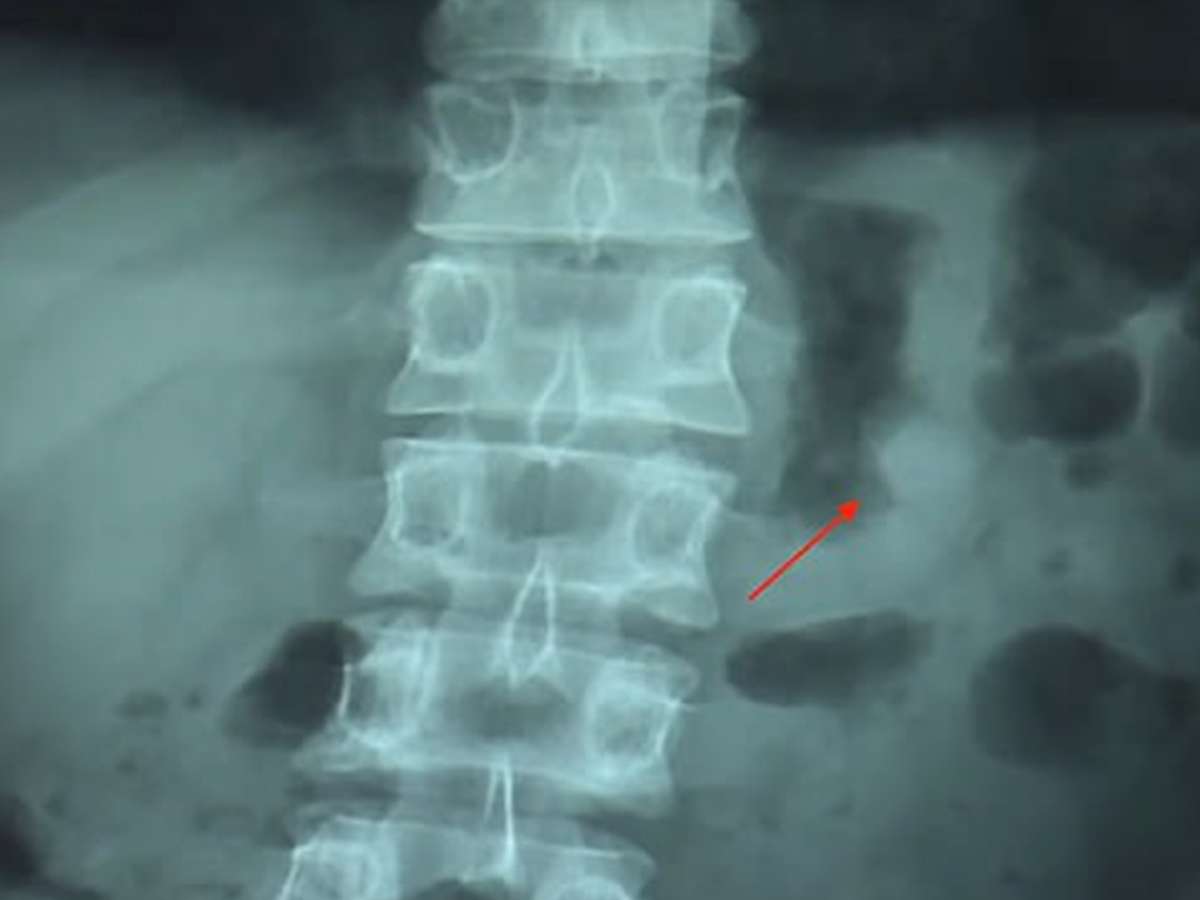

Foto: TecMundo

Levou algum tempo para ele perceber que o fone estava dentro de si. Com a suspeita e a preocupação de estar digerindo uma bateria de lítio no estômago, ele foi a um hospital e tirou a radiografia que você vê a seguir. A imagem confirmou que o fone realmente havia sido engolido durante o sono.

Imagem mostra o que parece ser a cabeça do fone dentro de Ben Hsu (fonte: AsiaWire/Daily Mail)